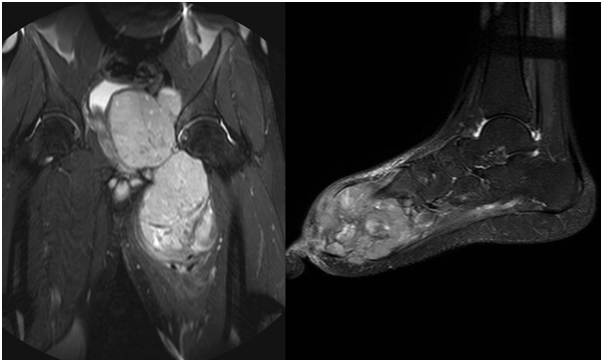

Figure 5 STIR coronal sequences of the pelvis, MRI images showing a heterogeneously hyperintense mass in the pelvis arising from the acetabulum.

Figure 6 MRI of the foot, sagittal STIR sequence showing a heterogeneous mass involving the fore and mid foot.